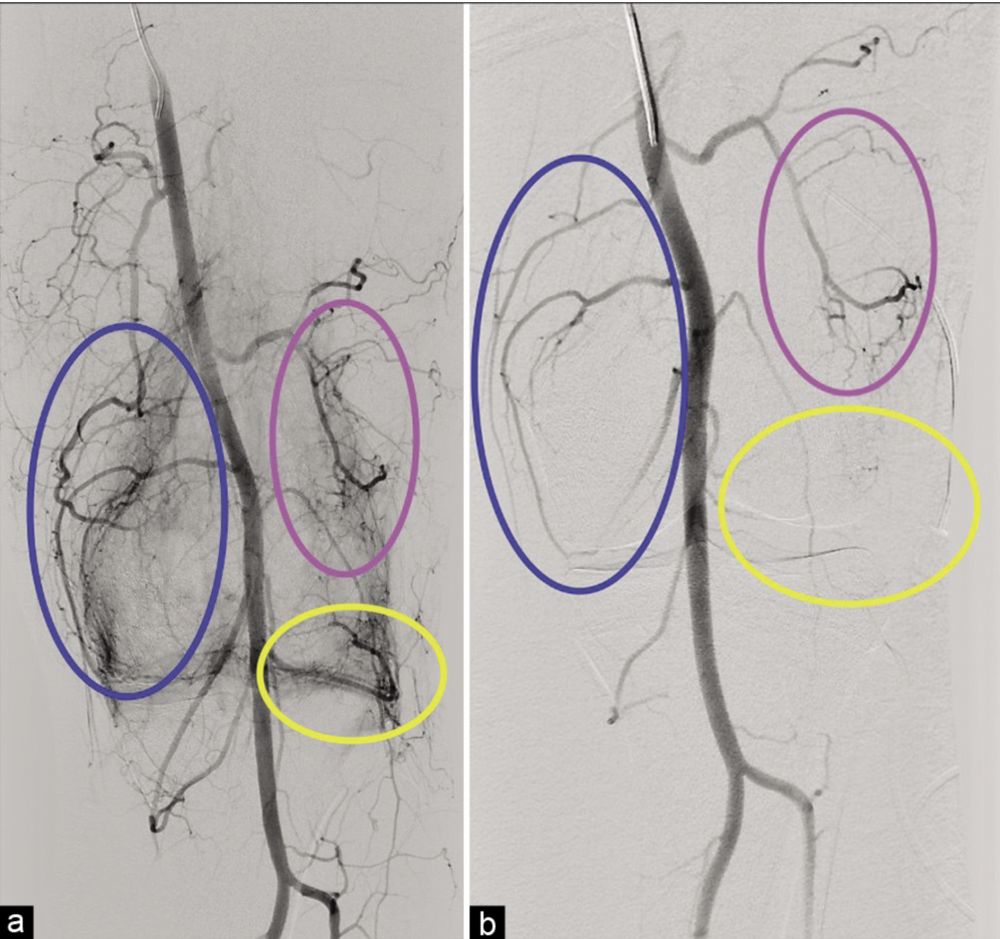

Attēlā: a. Hipervaskulārie apvidi ap ceļa locītavu atbilst aktieviem iekaisuma procesiem un ir sāpju avots. b. Uzreiz pēc embolizācijas redzama iekaisuma apvidu devaskularizācija.